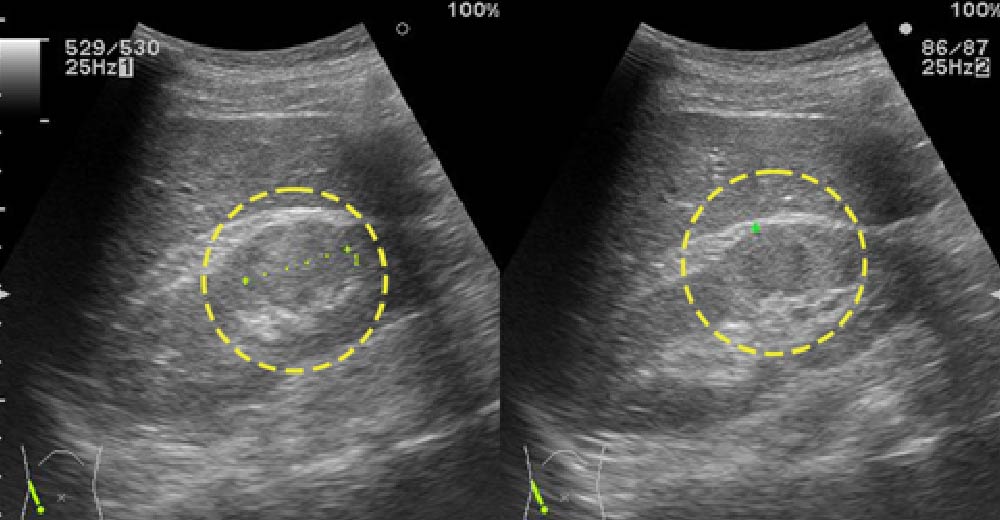

腎細胞がん症例です。

造影CTにおいて、不整な造影効果を伴う腫瘤が確認されます